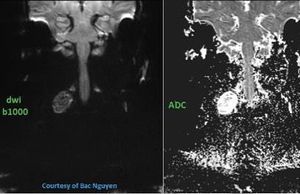

Diffusion-weighted imaging (DWI) is used to evaluate random, microscopic water motion within tissue, well known as Brownian motion. RESOLVE (figure) can be applied in head and neck MR Imaging for several clinical indications, providing higher image quality with less distortions and image blurring compared to SS-EPI, in reasonable acquisition times. Figure b1000 (left) & ADC map (right). RESOLVE allows the detection and characterization of head and neck tumor. Images courtesy of Bac Nguyen.